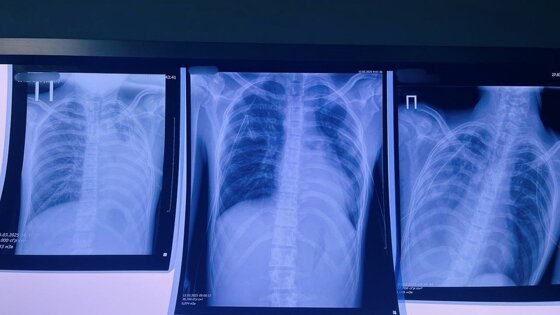

© Первоисточник

В Кирове 16-летний подросток несколько лет курил вейп. В результате в его легких образовались буллы (пузыри) в легких, которые внезапно разорвались, вызвав двусторонний пневмоторакс. Это потребовало экстренного вмешательства и перевода пациента в Федеральную клинику, где за жизнь ребенка продолжают бороться. Это не единичный случай.

Среди заболеваний появилось новое название «EVALI» – тяжелое поражение легких из-за токсичных веществ в жидкостях для вейпа, оно приводит буллезной болезни – образованию «пузырей» в легких, которые могут разорваться в любой момент. Особую опасность представляет ацетат витамина Е, при нагревании он превращается в клейкую массу, оседающую в легких. Случай в нашей клинике, произошедший с 16-летним подростком, – это тревожный сигнал. Когда мода оборачивается больничной койкой, стоит задуматься: нужно ли это «безопасное развлечение»? – задается вопросом заведующий хирургическим отделением детской областной больницы Виталий Лапшин.